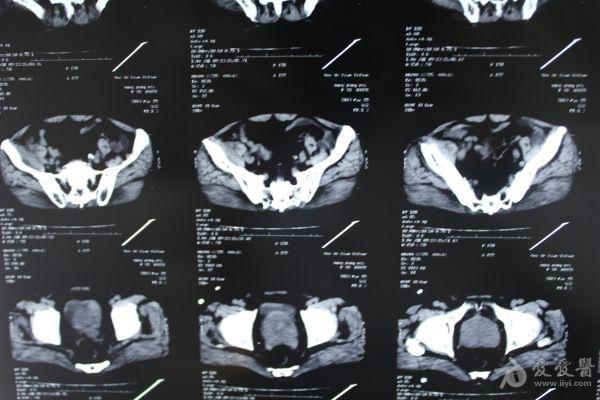

老年患者78岁,反复腰背部溃烂流脓4年,既往30年前曾在包块处排出蛔虫一条。CT: